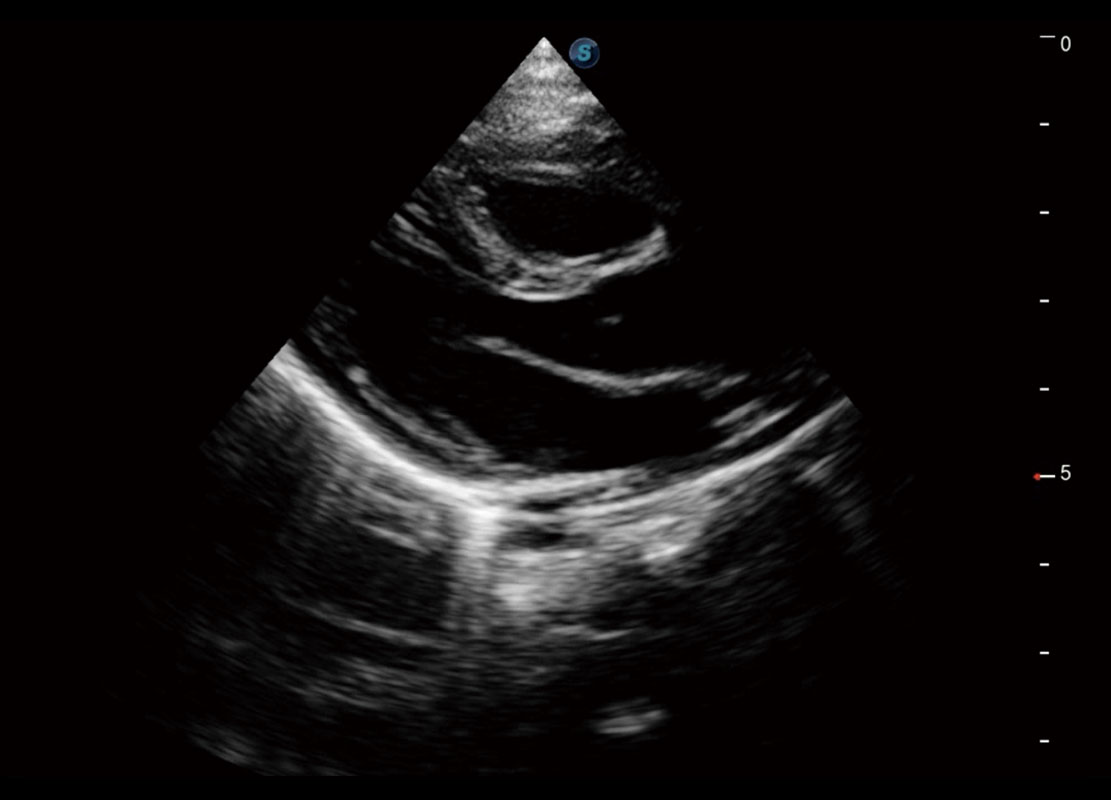

P60搭载一系列胎儿心脏成像技术,实现精细的胎儿心脏评估。

四腔切面

四腔心血流

右室双出口

胎心容积成像